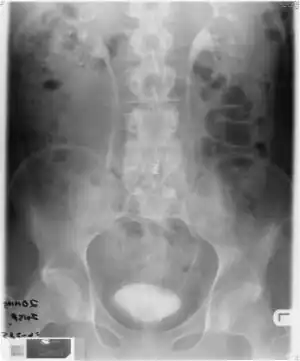

Klebsiella aerogenes is a nosocomial and pathogenic bacterium that causes opportunistic infections including most types of infections. The majority are sensitive to most antibiotics designed for this bacteria class, but this is complicated by their inducible resistance mechanisms,[5] particularly lactamase, which means that they quickly become resistant to standard antibiotics during treatment, requiring a change in antibiotic to avoid worsening of the sepsis.

Some of the infections caused by K. aerogenes result from specific antibiotic treatments, venous catheter insertions, and/or surgical procedures. K. aerogenes is generally found in the human gastrointestinal tract and does not generally cause disease in healthy individuals. It has been found to live in various wastes, hygienic chemicals, and soil. The bacterium also has some commercial significance – the hydrogen gas produced during fermentation has been experimented with using molasses as the substrate.